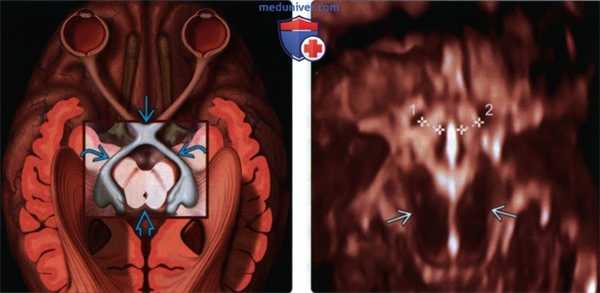

(Слева) На схематическом изображении показан проводящий путь зрительного анализатора. В рамку выделена область, которая видна при последующем 3D УЗИ. Она включает зрительный перекрест и зрительный тракт, обхватывающий ствол мозга.

(Справа) При 3D УЗИ под небольшим углом видны зрительные тракты (калиперы), расположенные спереди от ствола мозга В. Измерения сравнивают с нормативами. Иногда у плодов с отсутствующей ППП, но с нормальными размерами зрительного тракта не наблюдается нарушений зрения.